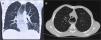

El estudio esofagogastroduodenal baritado (fig. 3) muestra progresión dificultosa del contraste a través de la unión esofagogástrica.